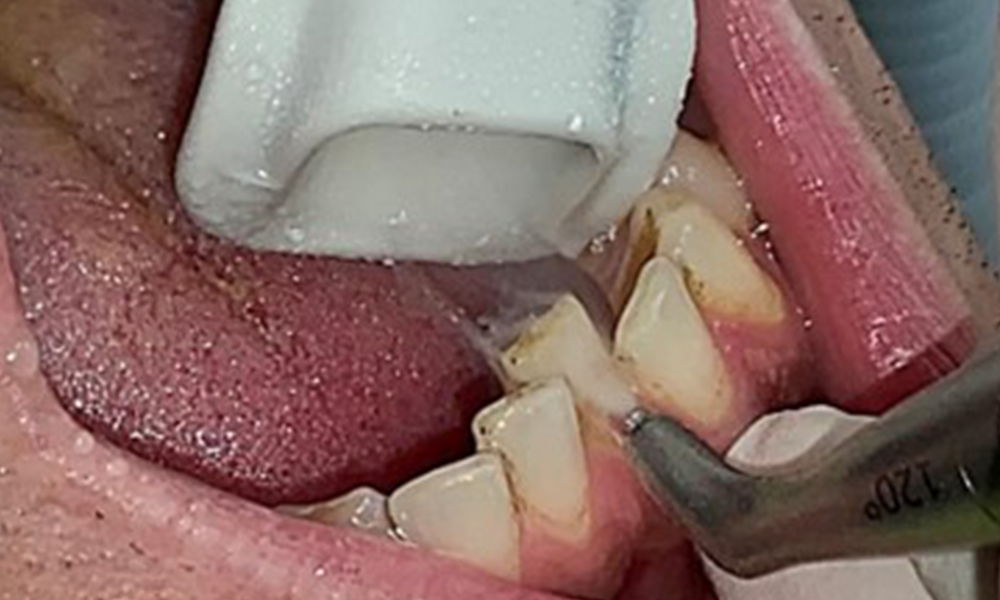

L'objectif serait de contrôler le risque de maladie en éliminant le biofilm supra-gingival et sous-gingival. Les instruments peuvent être sélectionnés en fonction des besoins du patient. Tout d'abord, le tartre et les concrétions doivent être éliminés à l'aide d'instruments ultrasoniques et/ou manuels (Fig. 10).

Utilisation d'un appareil à ultrasons piézoélectrique dans la zone linguale près de 36 (Proxeo Ultra, W&H, illustré ici).

Fig. 10 Utilisation d'un appareil à ultrasons piézoélectrique dans la zone linguale près de 36 (Proxeo Ultra, W&H, illustré ici)., © Dr R. Krapf